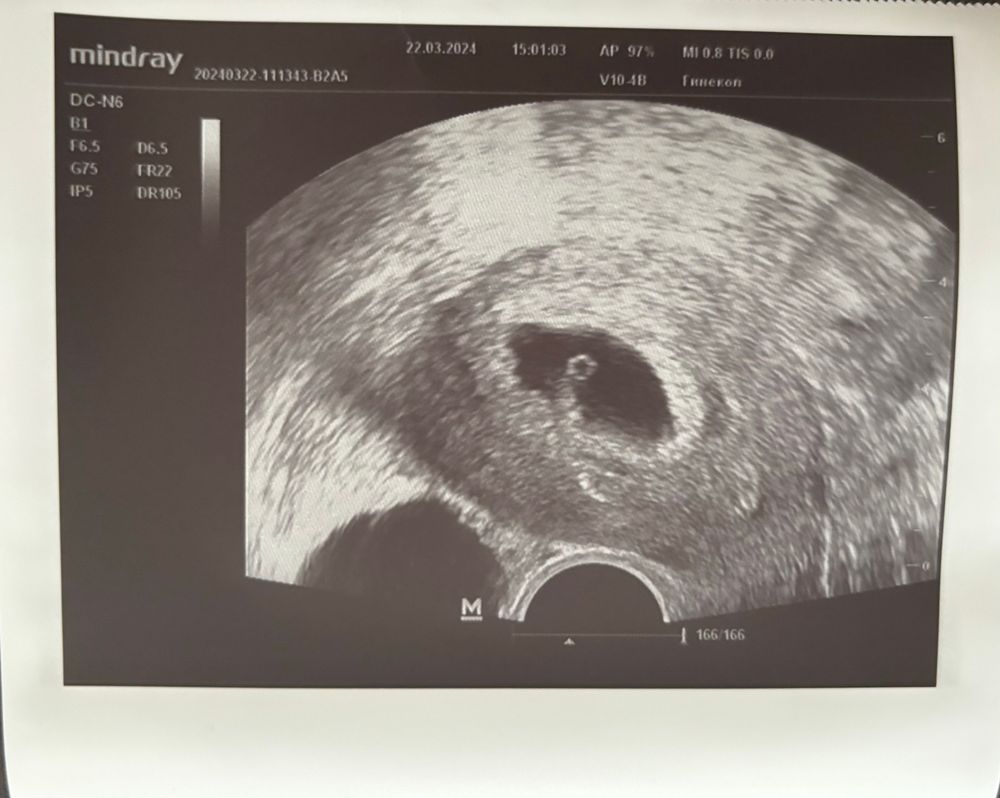

21дпп результат УЗИ

Результаты следующие: ПЯ 18мм, ЖМ 3мм, все хорошо, малюсенький эмбриончик - звездочка на месте 😍 Репродуктолог сказала, что если будут выделения, то Клексан отменим на неделю, если нет, то пока подождём. Из поддержки добавила дюфастон по 1т 2 р/д. Я немного выдохнула, надеюсь дальше все будет хорошо 😊